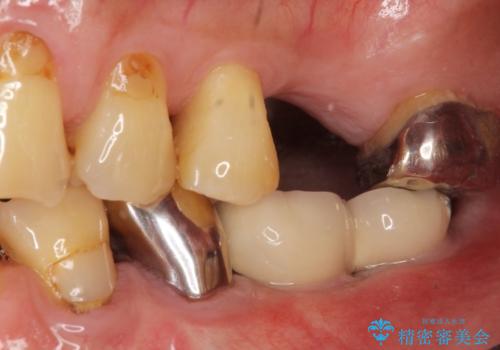

奥歯のインプラント ソケットリフト 60代男性

- 奥歯のインプラントをご希望し、来院された患者様です。

精査したところ上顎骨の厚みが薄かったため、ソケットリフト(上顎洞底挙上術)を併用してインプラント治療を行いました。

審美的・機能的な仕上がりに喜んで下さいました。

また、半年という比較的短期間でインプラント治療が終わったことにもご満足頂けました。

インプラントの種類:スプライン ツイスト (保証期間:5年)

クラウンの種類:ベレッツァクラウン (オールセラミック)

固定様式:セメント固定